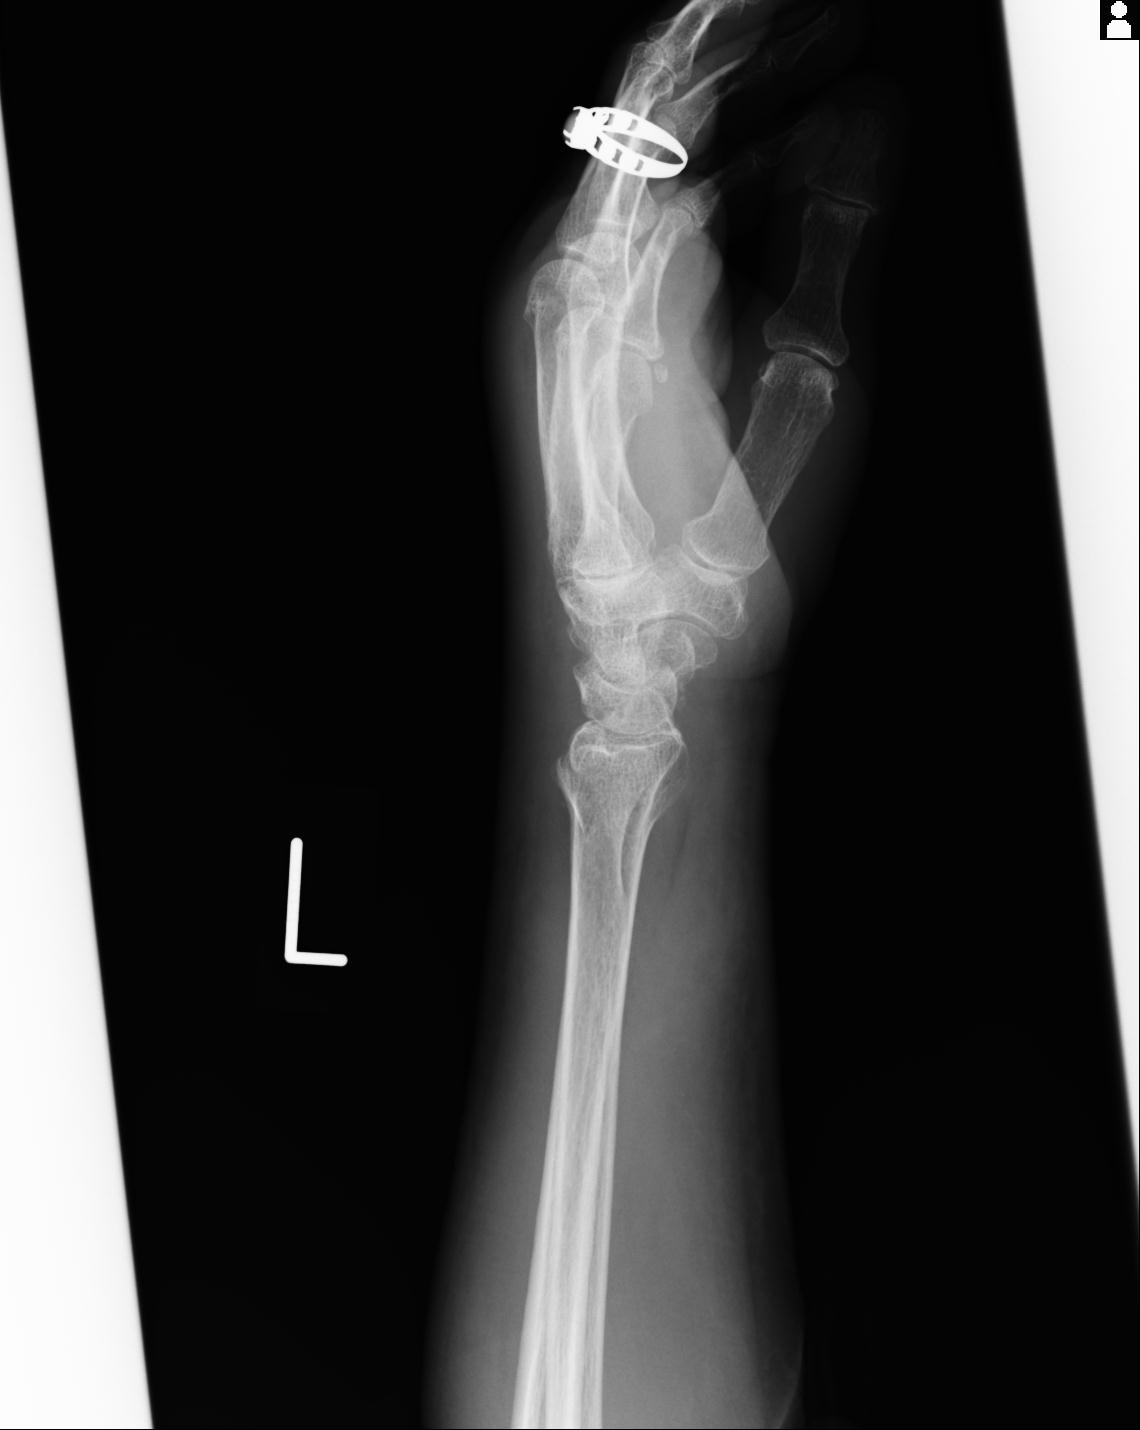

110211 1/6 1/8 左前腕 4R 15歳男性 橈骨骨幹部骨折